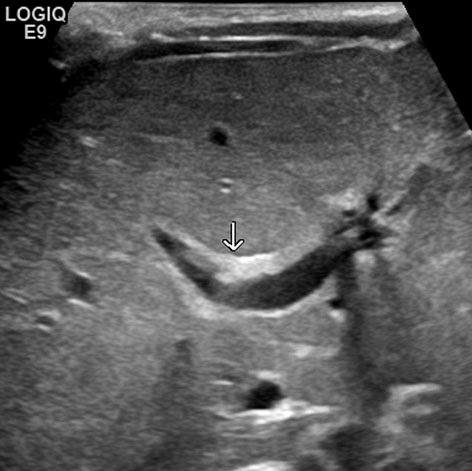

Galgangatresie moet in Nederland eerder worden herkend. Vroegtijdige detectie verbetert de uitkomst voor patiënten. Zorgverleners in de eerste lijn kunnen galgangatresie signaleren met behulp van de ontlastingskleurenkaart. Bloedonderzoek (direct en totaal bilirubine) is nodig bij alle kinderen met ontkleurde ontlasting na de geboorte en neonaten die op de leeftijd van drie weken nog geelzien. Bij geconjugeerde hyperbilirubinemie en een verhoogd gamma-glutamyltransferase (γGT) moet de diagnostiek worden gecoördineerd in overleg met een kinderhepatologisch centrum voor snelle doorverwijzing. Daar kan de diagnose galgangatresie worden bevestigd met een leverbiopt en volgt zo snel mogelijk een Kasai-operatie. Bewustwording van de diagnose galgangatresie is essentieel in de hele zorgketen.